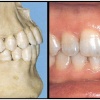

Diasteem

Diasteem – vahe esimeste hammaste vahel. Esineb 50%-l 6-8 aastastel lastel. Kuni 2 mm diasteemi puhul on, peale lateraalse intsisiivi ja silmahamba lõikumist, võimalik diasteemi iseeneslik sulgumine. Diasteem, mille suurus...